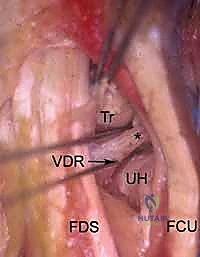

2. The Volar Ulnar Portal (VU)

- Location: Located underneath the ulnar border of the flexor tendons (specifically the flexor carpi ulnaris, FCU, and flexor digitorum sublimis, FDS) at the level of the proximal wrist crease.

- Anatomy: The interval between the FCU and FDS tendons.

- Neurovascular Risks: HIGH. The ulnar nerve and ulnar artery are immediately radial to the FCU tendon. The palmar cutaneous branch of the ulnar nerve is also vulnerable. Extreme caution and meticulous blunt dissection are mandatory.

- Function: Indicated for visualizing and débriding palmar tears of the lunotriquetral ligament (LTIL). It aids in the repair or débridement of dorsally located TFCC tears, especially when triangulation from dorsal portals is difficult. It also assesses the dorsal radioulnar ligament, the ECU subsheath, and the radial TFCC attachment.

3. The Triquetrohamate Portal (T-H)

- Location: Enters the midcarpal joint at the level of the triquetrohamate joint, ulnar to the ECU tendon. Its entry site is both ulnar and distal to the midcarpal ulnar portal.

- Anatomy: Directly accesses the articulation between the triquetrum and hamate.

- Neurovascular Risks: Branches of the dorsal cutaneous branch of the ulnar nerve are most at risk here.

- Function: A special-use portal for specific pathology localized to the triquetrohamate joint.